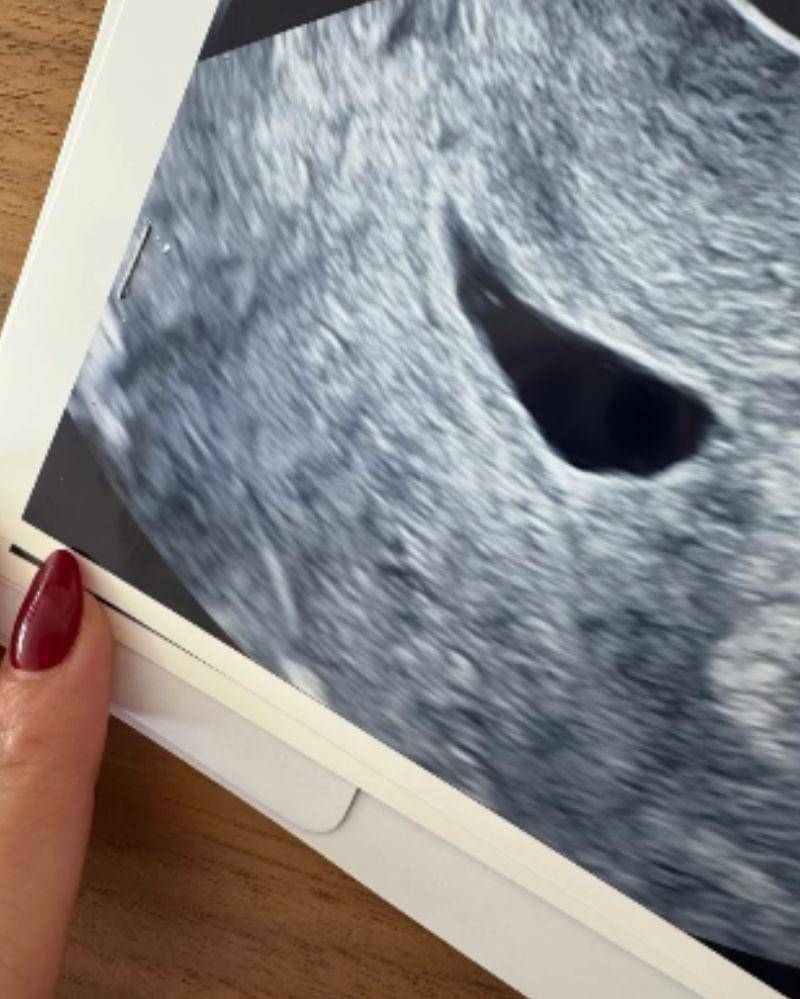

3. Bagikan foto janinnya, Nikita percaya ia bisa mendapatkan yang lebih baik

Selain foto dirinya dan hasil ultrasound bayinya, Niki juga membagikan sebuah tabung dengan tutup berwarna merah muda.